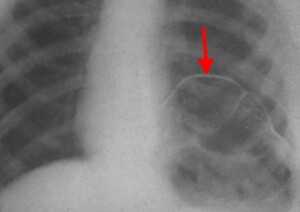

Ателектаз верхней доли правого легкого.

Оцените ниже лежащие изображения, а после продолжите чтение.

- Трехгранное затенение.

- Подъем правого корня легкого

- Облитерация загрудинного пространства (указано стрелкой).

Также очень частым проявлением ателектаза является подъем диафрагмы, что хорошо визуализируется на ниже представленной рентгенограмме (указано синий стрелкой).

У данного пациента карцинома легкого с билатеральным метастазированием в легкие (указано красными стрелкам).